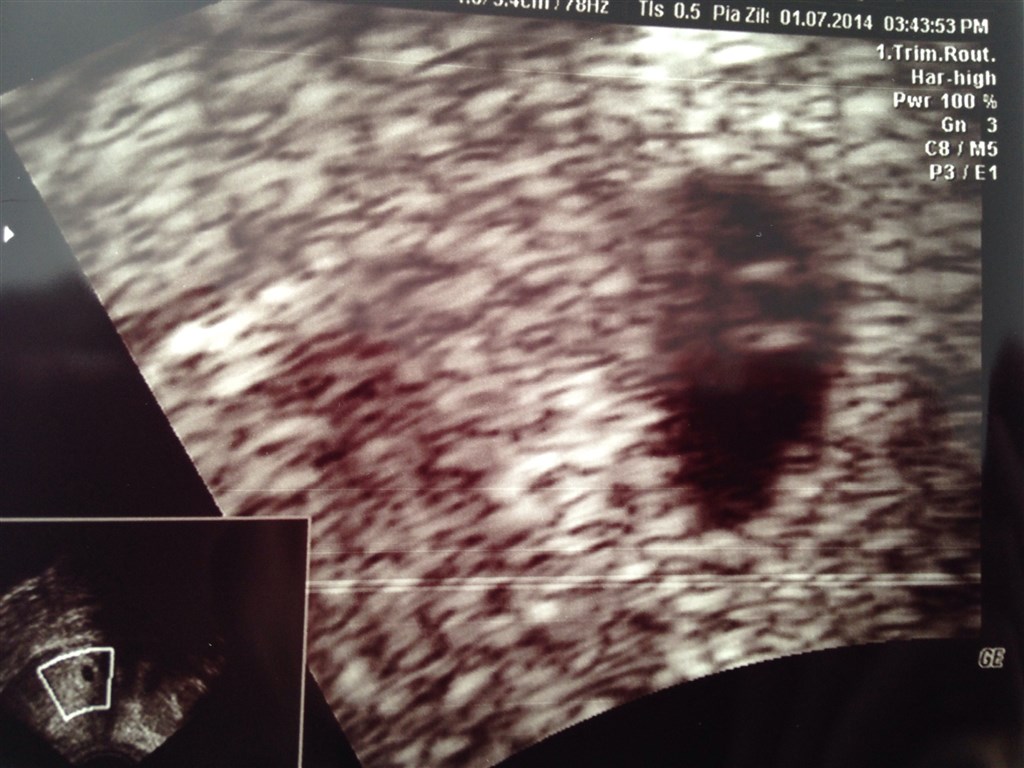

Hun scannede både på maven og indeni.

Altså, ud fra fotoet at dømme, tror jeg desværre ikke at du får gode nyheder til næste scanning... MEN jeg er jo ikke ekspert.

Men det virker meget underligt at hun ikke bare melder klart ud og siger at der ikke længere er liv - hvis det er dét hun mener? Det virker som om hun har været super vag?